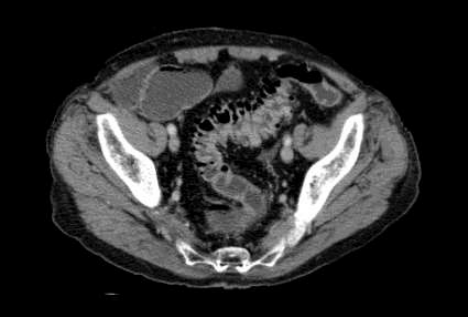

Homem, previamente hígido, 52 anos. Admitido na emergência com mal-estar e dor em FIE há 48h. Nega febre.

Leucócitos 9.800. Realizou TC de abdome abaixo.

Após parecer da cirurgia geral, qual o diagnóstico e a conduta que devemos implementar?